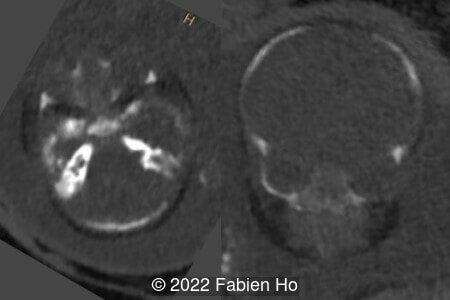

A CT scan was subsequently performed at 32 weeks gestation

The prenatal CT scan showed:

- Low bone density of skull and lower limbs

- Moderately narrowed and bell-shaped thorax

- Numerous bone calluses of the posterior arcs of the ribs

- Normal bone density of the spine

- No platyspondyly

- Normal pelvis without iliac spine or other anomaly

- Very short long bones with curved femurs, tibias and fibulas. The curvature of the long bones reaches a 90° angle concerning for fracture. Upper limbs are moderately curved without fracture.